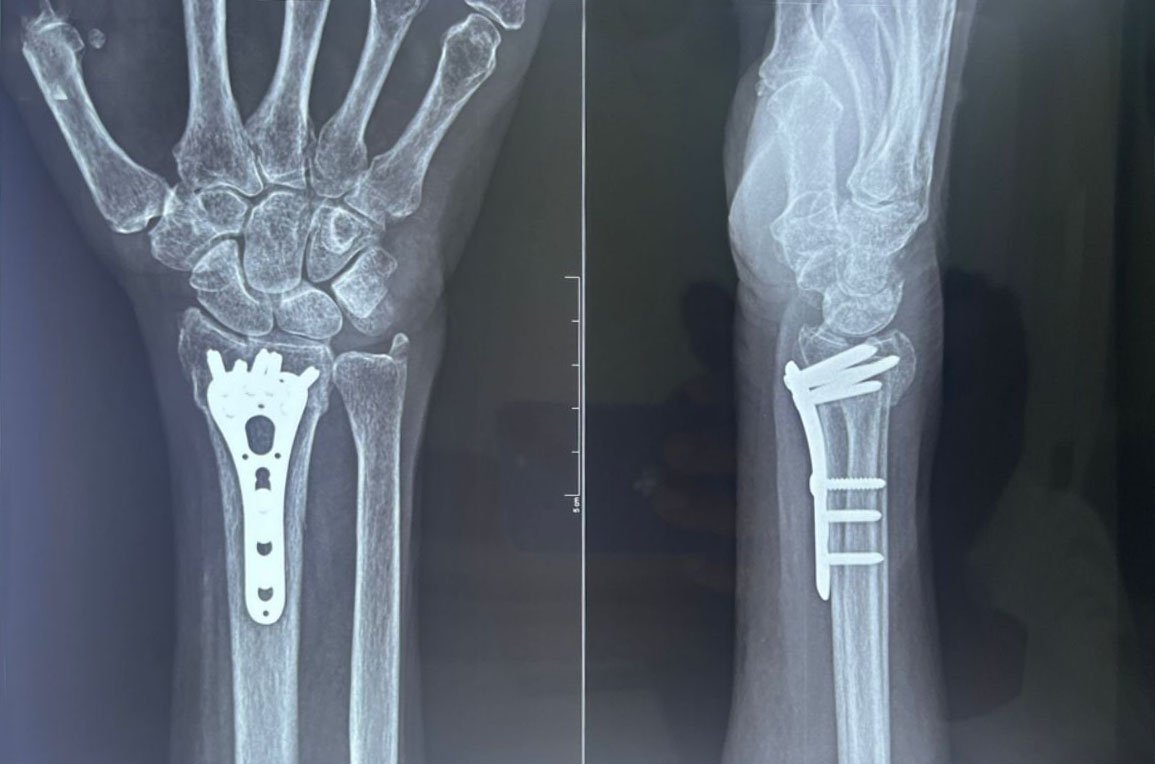

- Fracture Treatment: We specialize in the surgical and non-surgical treatment of

fractures, utilizing advanced techniques to ensure optimal healing and recovery.

- Expertise in Trauma Care: Dr. Zambare is highly skilled in managing complex trauma

cases, including multi-limb injuries and severe fractures. His expertise ensures that patients receive

precise and effective treatment for their injuries.

- Imaging and Diagnostic Services: We offer comprehensive imaging and diagnostic

services, including high-resolution X-rays and orthoscannograms, to accurately diagnose and plan

treatment for orthopaedic conditions.